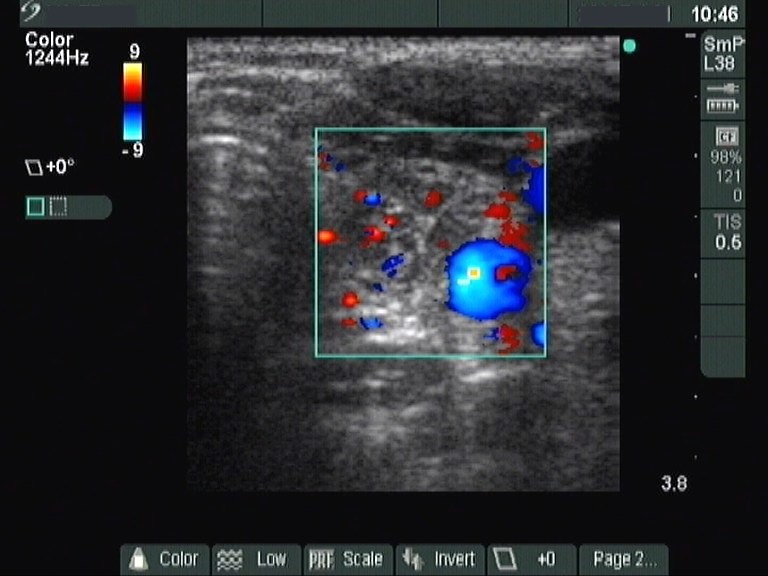

Ultrasonography: revealed hypoechogenic inhomogeneous thyroids. There was a moderately hyperechogenic nodule in the left lobe. The nodule presented a halo sign and perinodular blood flow.